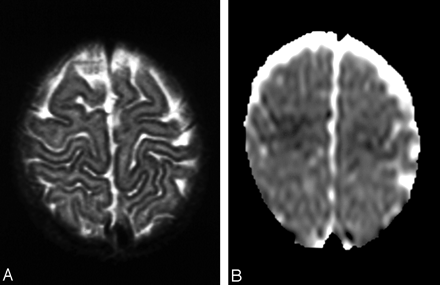

Patient 5.

A, T2-weighted image shows subtle abnormal findings, slight hyperintensity of the anterior frontal region, and localized areas of blurring of the cortical stripe.

B, DWI (ADC) indicates restricted diffusion compatible with cytotoxic edema.

With therapy, improvement was observed in the brain stem in two patients, in the periaqueductal region in three patients, in the thalami in two, in the mammillary bodies in one, and in the frontal lobes in three. Enhancement after the injection of contrast agent was seen in the tectum in one patient and in the frontal cortex in two. DWIs showed cytotoxic edema in the brain stem in one patient, in the thalamus in two patients, in the basal ganglia in three, and in the frontal cortex in three (Figs 1E and 4B).